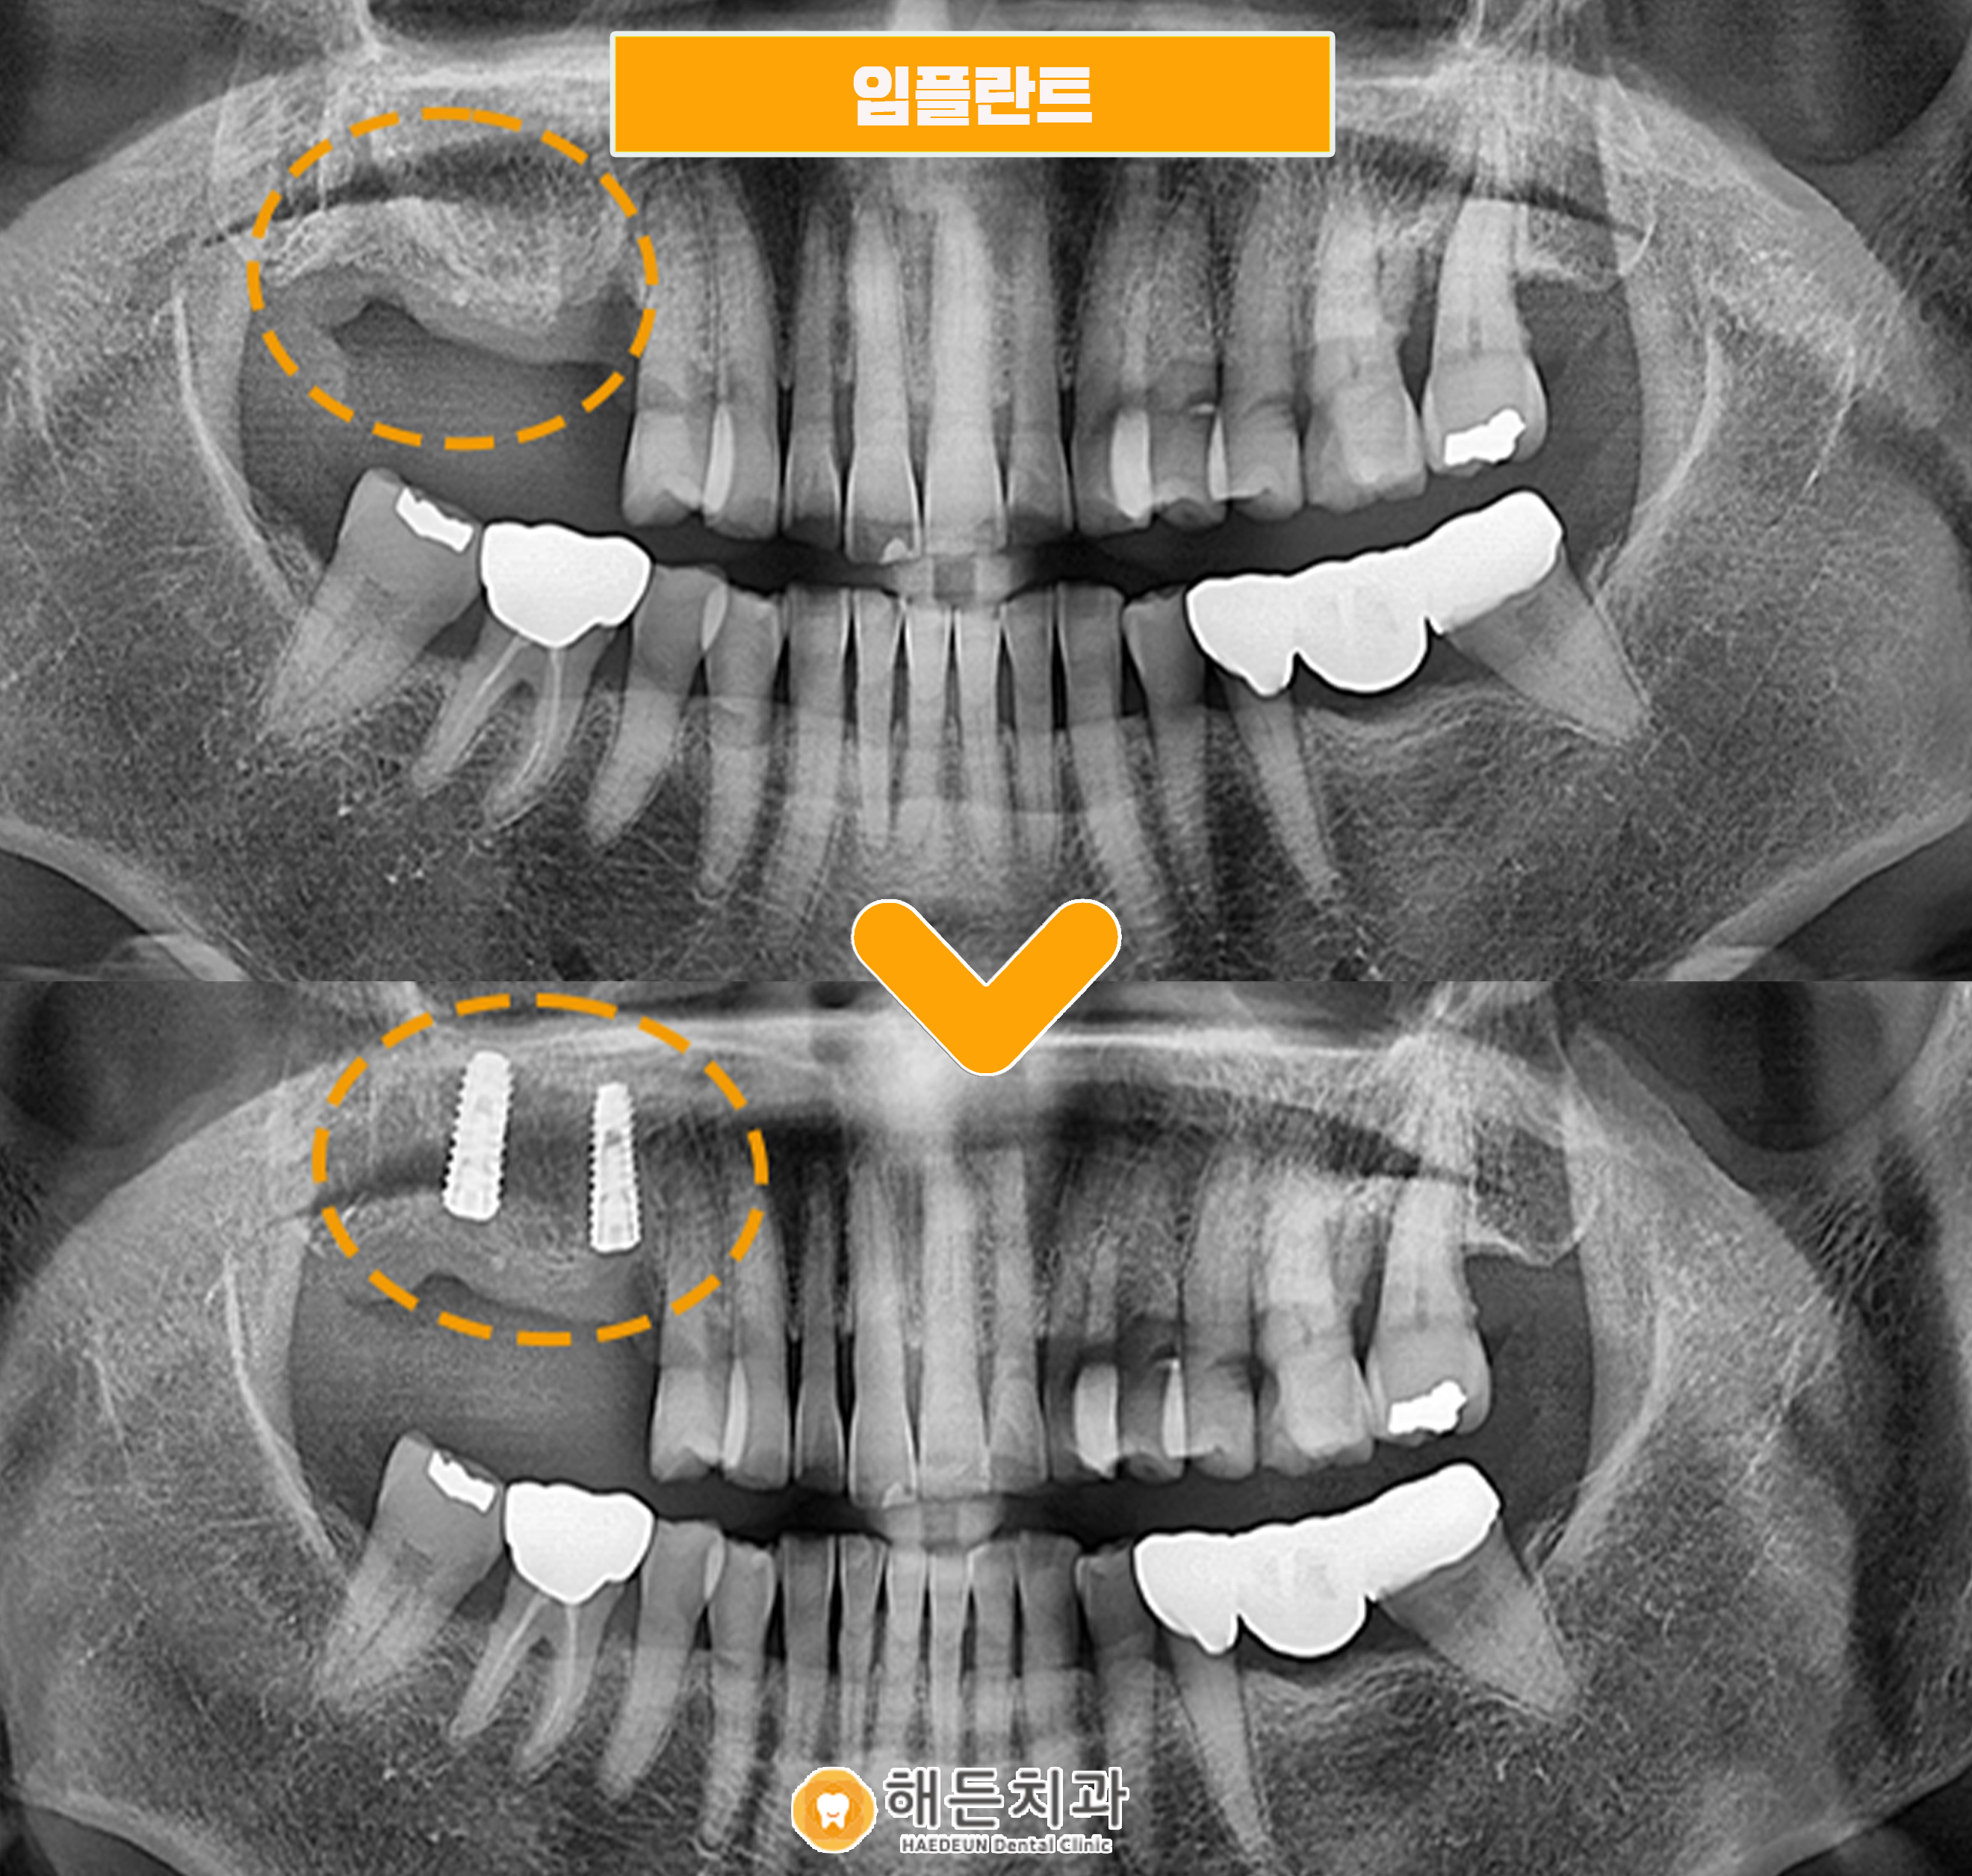

임플란트 식립 후 사진입니다.

현재 치아 뿌리 역할을 하는 인공치근인 픽스처만 식립되어 있는 상태이며, 커버스크류를 체결해놓은 상태인데요.

임플란트는 잇몸뼈에 인공치근을 식립한 뒤,

뼈와 단단하게 붙을 수 있는 충분한 기간을 기다려 준 후 최종보철물(크라운)을 올려주게 됩니다.

임플란트는 정밀한 판단을 바탕으로 수술이 진행되어야 하는데요.

본원에서는 다양한 디지털 장비를 바탕으로 식립 전 계획을 꼼꼼하게 수립하고 있습니다.

잇몸뼈의 상태나 신경관의 위치, 인접 치아들과의 관계, 상악동의 위치 등

여러가지 구강 내 해부학적 구조물을 파악하여, 임플란트의 위치 및 각도 등의 치료 전 계획을 수립하고 있답니다. 👍